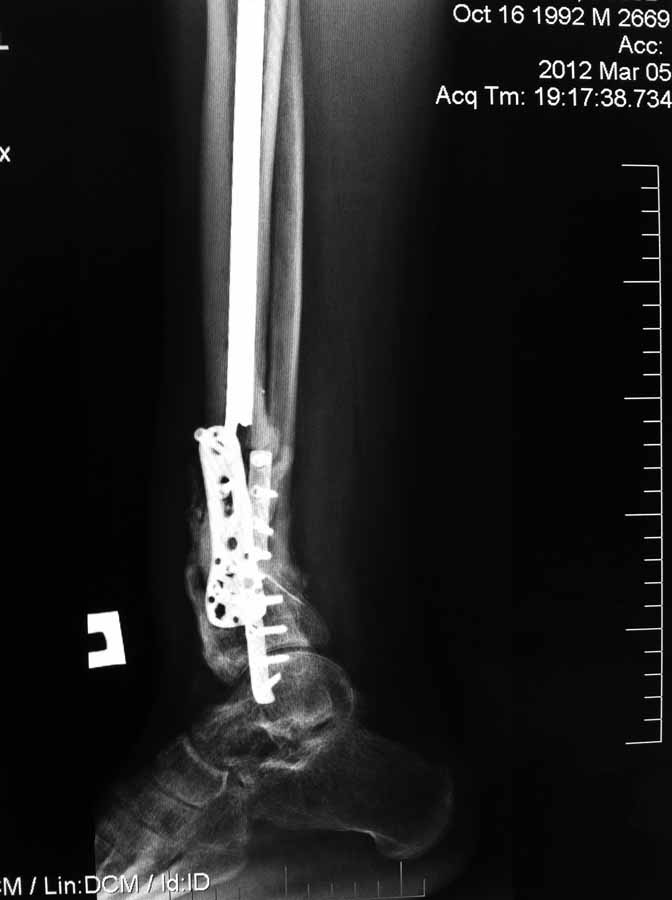

[Ortho] Несращение дистального отдела костей голени

Вчера не вышло выслать все фото. Последние снимки более более драматичные, как раз с куском проксимального стержня и пластиной что не к месту!

Имя     : IMG_0324.JPG

Тип     : image/jpg

Размер  : 58502 байтов

Url     : http://weborto.net:8080/pipermail/ortho/attachments/20120504/3cea5761/attachment-0002.jpg